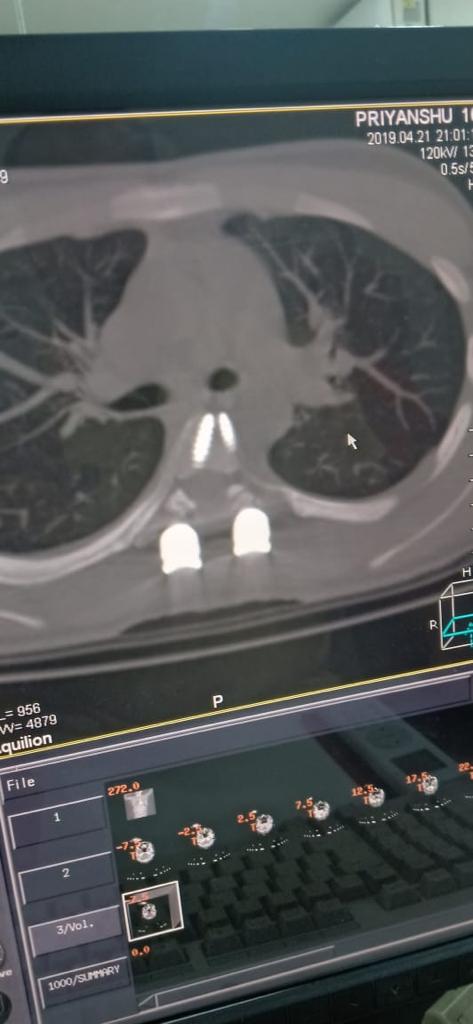

Cases